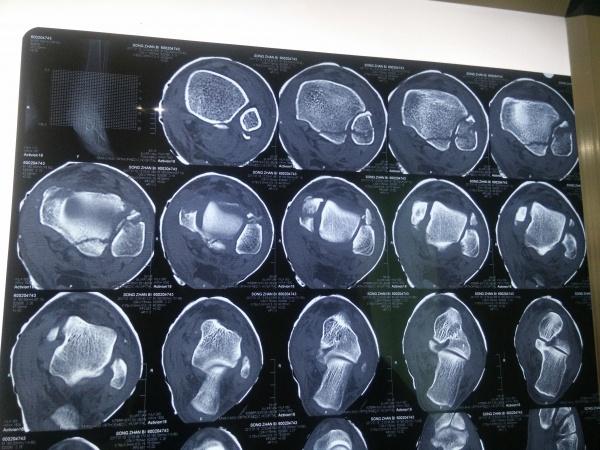

左三踝骨折手术治疗

患者女,外伤后左踝关节活动受限1小时入院,

入院后查体:左踝关节肿胀,活动受限,行DR及左踝关节CT检查,如下图,手术待肿胀消退后行手术治疗,目前愈合良好,请问问各位老师,好久可以下地呀, 下胫腓联合镙钉3个月取呀,

这个下胫腓螺钉真的没有必要打,另外后踝的两枚螺钉怪怪的,从后往前打的,看着钉子帽偏内侧,这个应该在外侧才对,